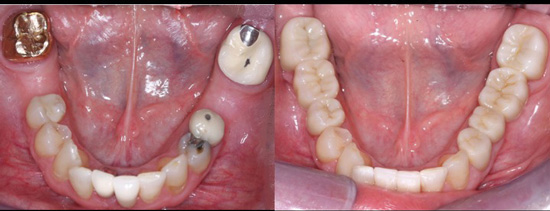

• Use resin-modified glass ionomer (RMGI) cement for zirconia restorations when the tooth preparations have near-optimum characteristics. See Figures 4 through 6 for examples of these characteristics. Most clinicians and researchers would agree that the tooth preparation should be at least 4 mm in height from the gingival margin to the occlusal table, and that the lack of parallelism of the preparation walls should be up to, but not more than, 20 degrees from the long axis of the tooth being prepared.

Figures 4-6: Images showing an adequate impression, the die of an adequate tooth preparation, and the resultant full-zirconia crowns.

Figure 4

Figure 5

Figure 6